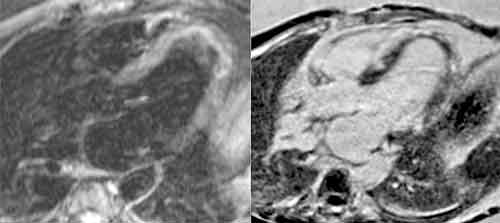

Ett icke-invasivt sätt att stödja diagnosen myokardit är magnetkameraundersökning av hjärtat (MR-hjärta), och Lake Louise-kriterierna kan användas [3]. Enligt ESC är bilden vid MR-hjärta överstämmande med myokardit om den hos patient med kliniskt misstänkt myokardit uppfyller minst 2 av 3 Lake Louise-kriterier:

• högsignalering på T2-viktade bilder (tyder på ödem)

• tidig uppladdning av gadoliniumkontrast (tyder på ökad blodgenomströmning)

• sen uppladdning av gadoliniumkontrast (tyder på ärrvävnad).

MR-hjärta kan också visualisera inflammation och svullnad i perikardiet. Positronemissionstomografi (PET) rekommenderas inte rutinmässigt i utredning av myokardit, men fluorodeoxiglukos-PET kan vara värdefull vid misstänkt hjärtsarkoidos.

MR-hjärta vid myokardit. Till vänster: Trekammarvy med T2-viktade bilder visar ökad signalering tydande på ödem. Till höger: Trekammarvy (gadoliniumkontrast) under sen fas visar retention av kontrast i ärrvävnad.